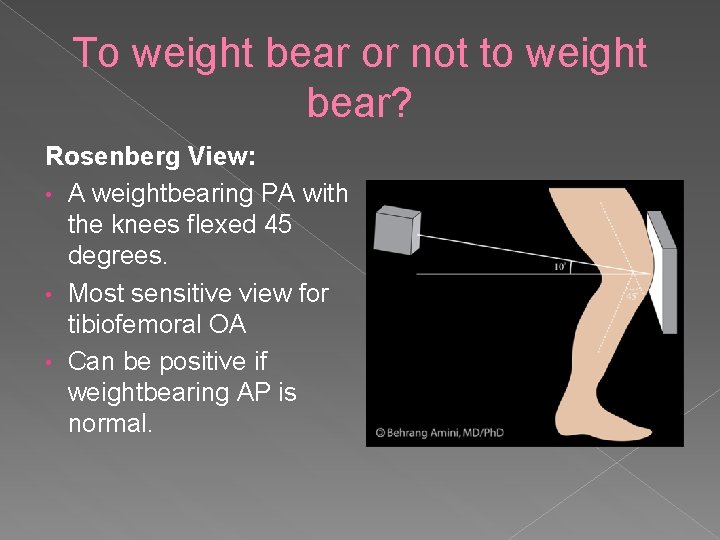

To weight bear or not to weight bear? Rosenberg View: • A weightbearing PA with the knees flexed 45 degrees. • Most sensitive view for tibiofemoral OA • Can be positive if weightbearing AP is normal.